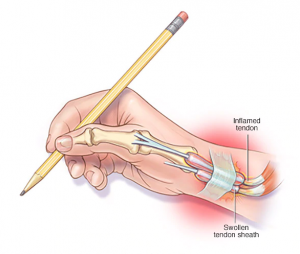

‘Gamer’s Thumb’ is one name given to a condition called de Quervain’s Tenosynovitis which is a condition where the tendons that move your thumb become inflamed.

When you grip, grasp, clench, pinch or wring anything in your hand, two tendons in your wrist and lower thumb normally glide smoothly through the small tunnel that connects them to the base of the thumb. Repeating a particular motion day after day may irritate the sheath around the two tendons, causing thickening and swelling that restricts their movement.

The inflammation in the thumb is a result of severe repetitive strain on the tendons which leads to pain and limited movement of the thumb. Gaming is a common cause of repetitive strain on the thumb, so De Quervain’s Tenosynovitis is often called ‘Gamer’s Thumb’.

Continuous use of your smartphone for gaming, messaging, social media and other usages is another way that this condition can develop. Although smartphone usage is a common cause, gaming may put more intense strains on your thumbs for longer periods of time.